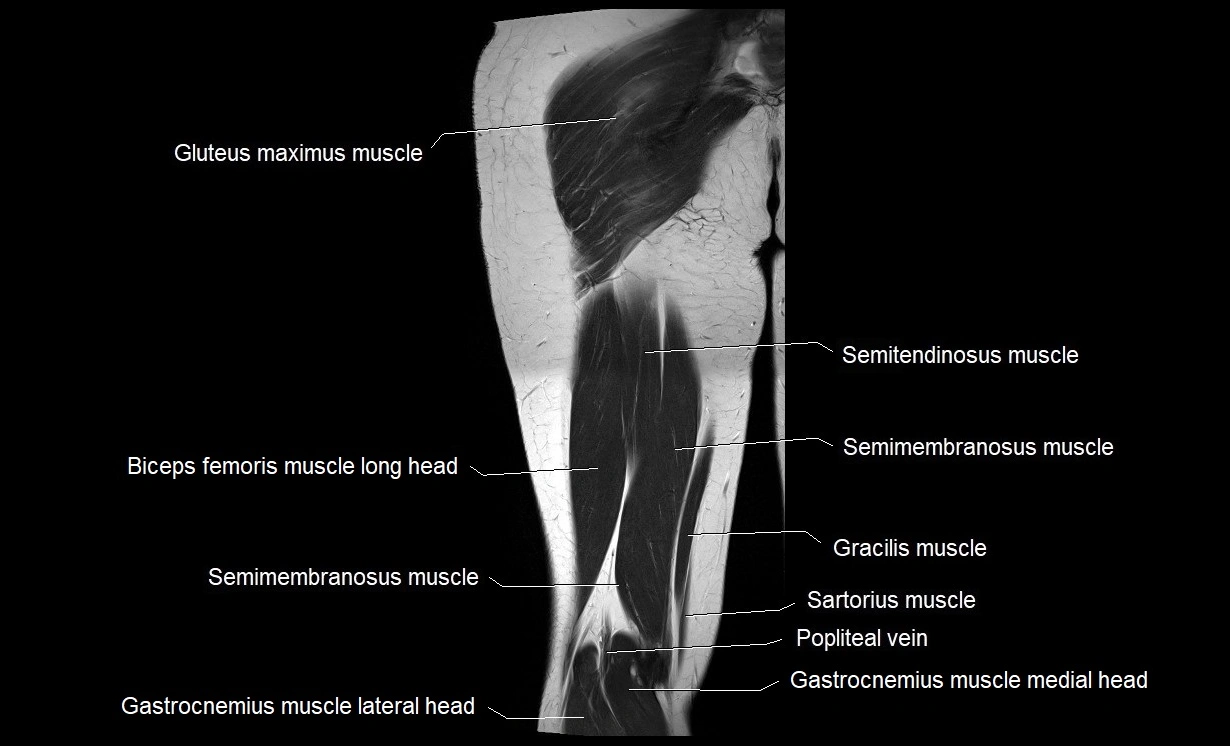

- Biceps femoris muscle (Long head)

- Gastrocnemius muscle

- Gluteus maximus muscle

- Gracilis muscle

- Medial head of gastrocnemius muscle

- Popliteal vein

- Sartorius muscle

- Semimembranosus muscle

- Semitendinosus muscle